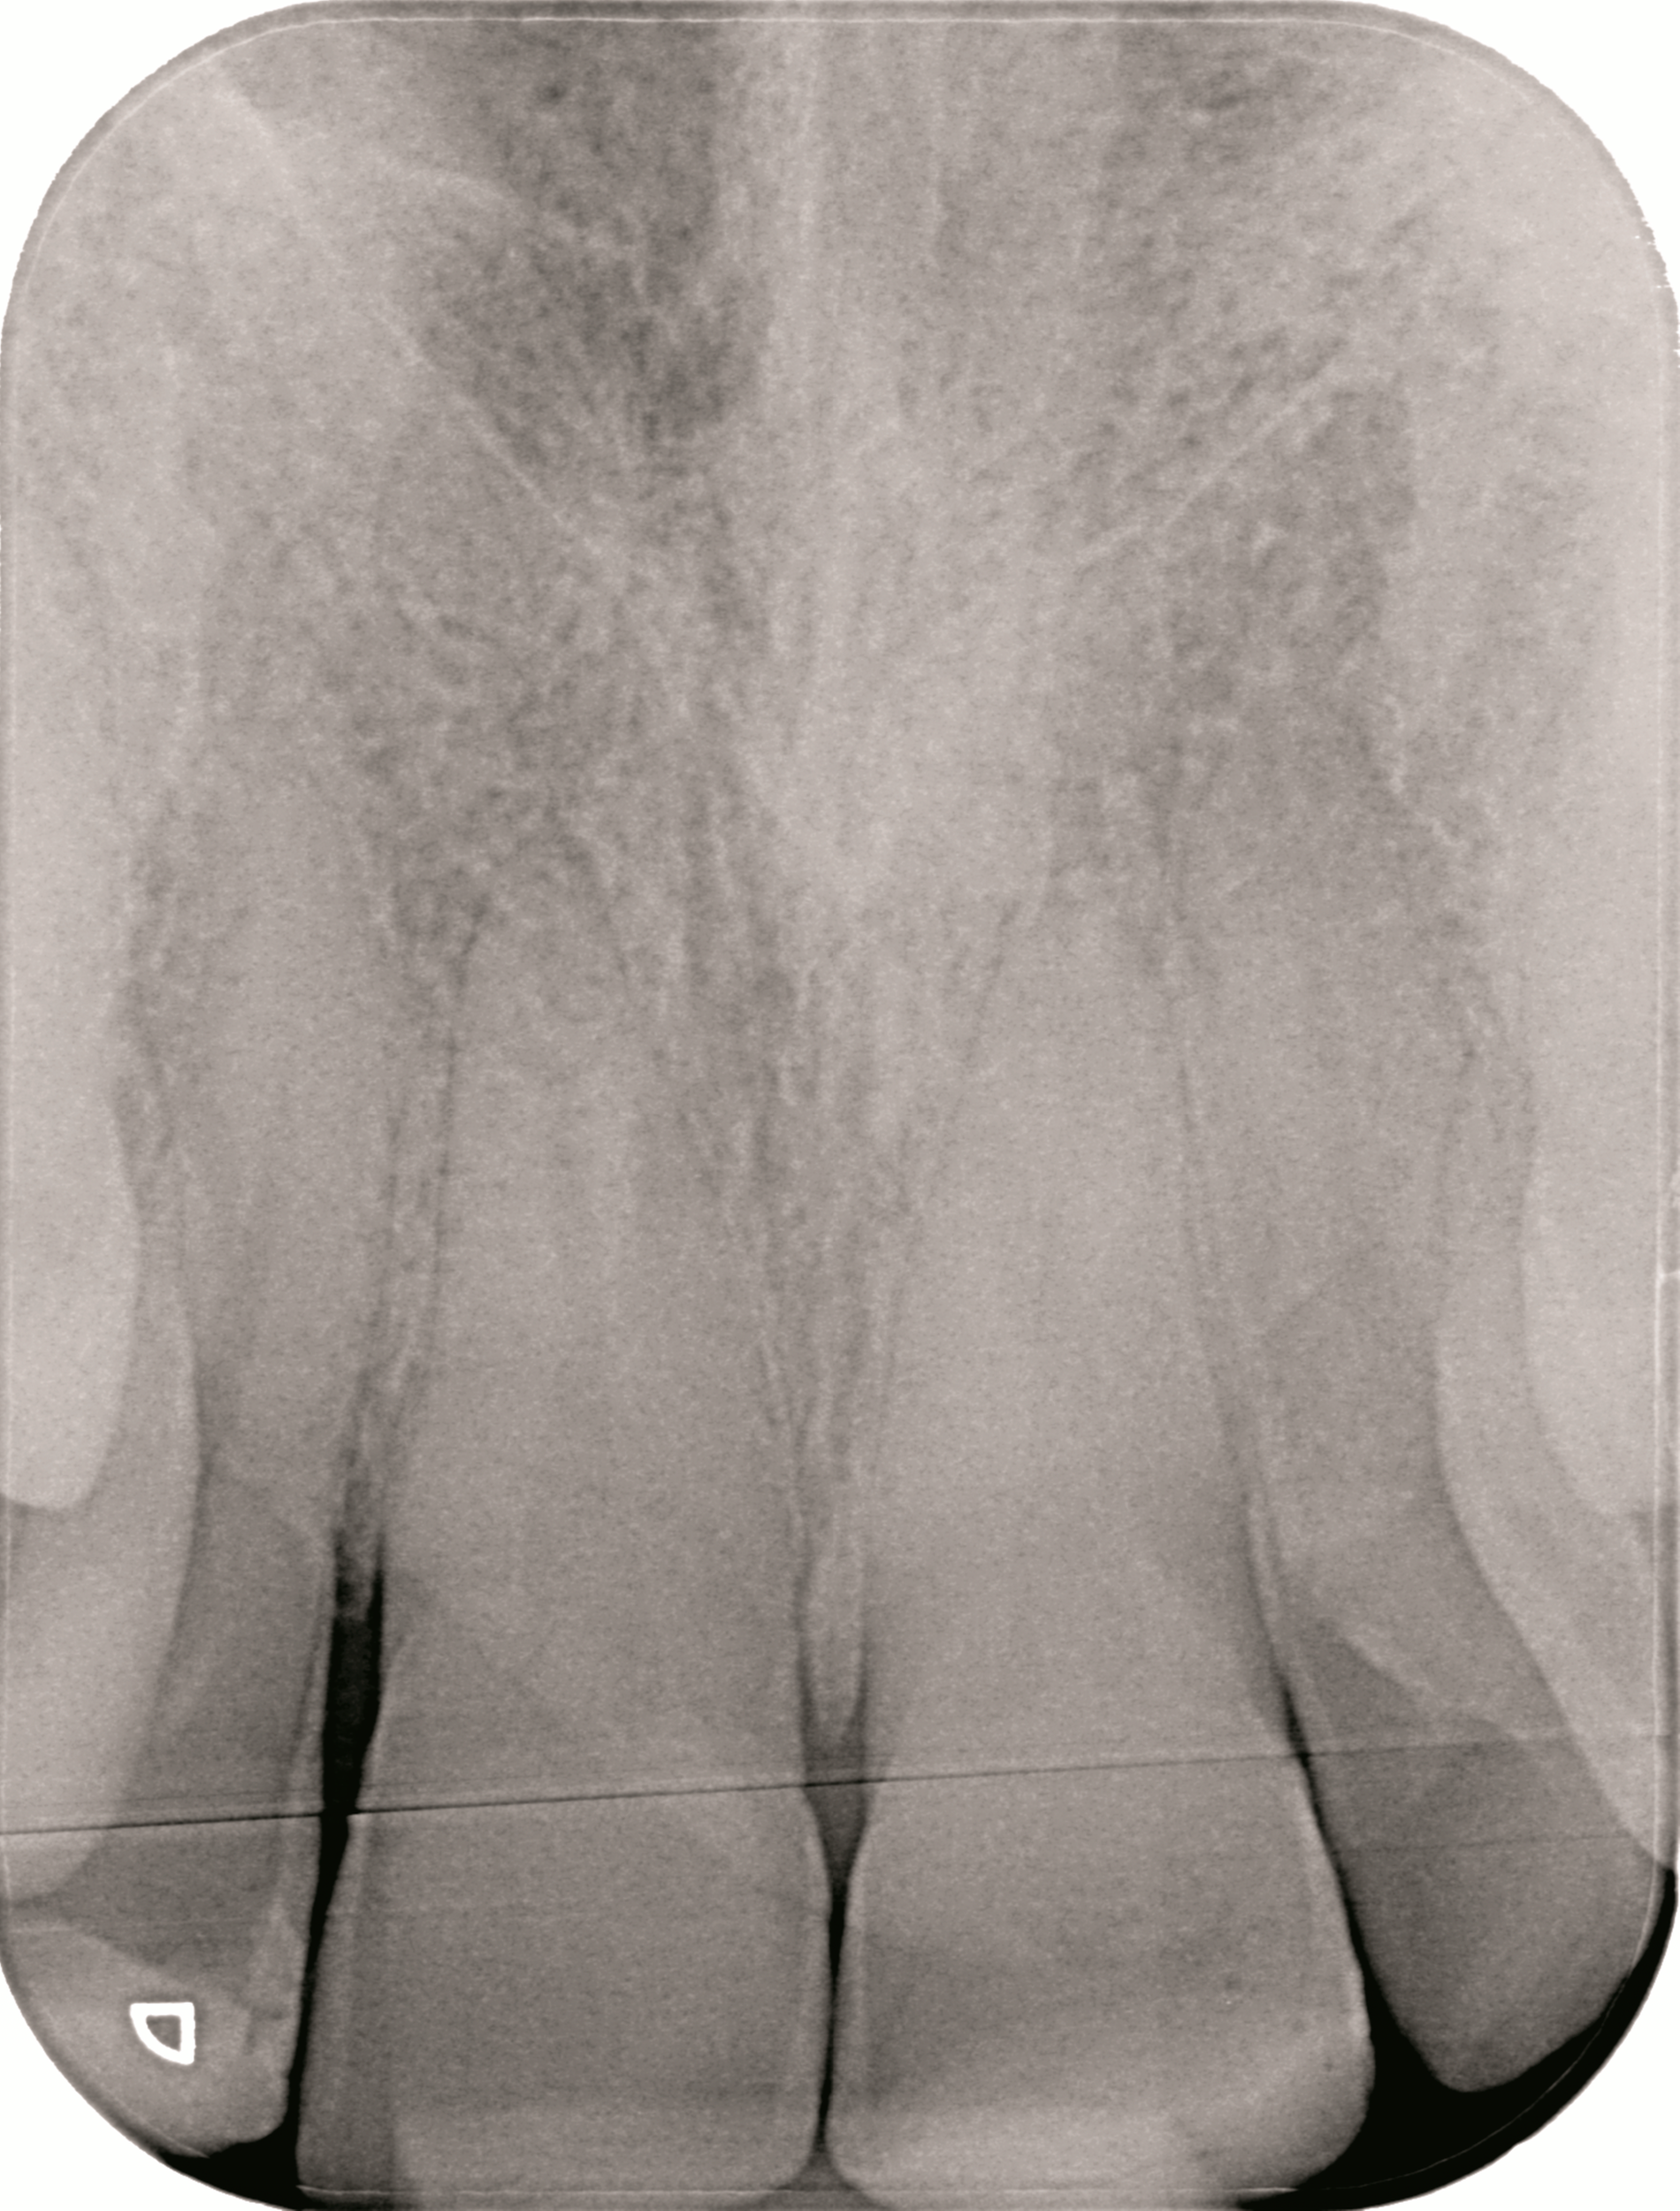

Um potenzielle Komplikationen nach einem Zahntrauma möglichst frühzeitig zu erkennen, werden entsprechend den Empfehlungen der S2k-Leitlinie regelmäßige röntgenologische und klinische Nachkontrollen durchgeführt. Exemplarisch sind hier die Röntgenbilder nach drei Monaten und 1,5 Jahren dargestellt (Abbildung 3).